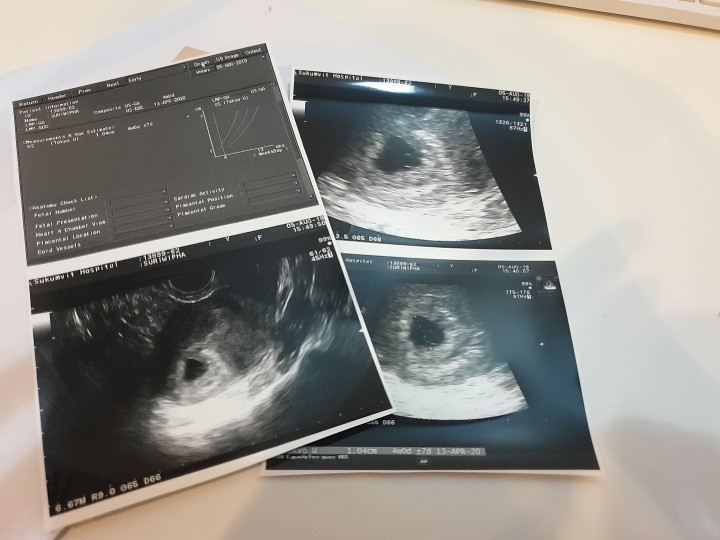

ซาวด์ตอน 14wค่ะ 😊